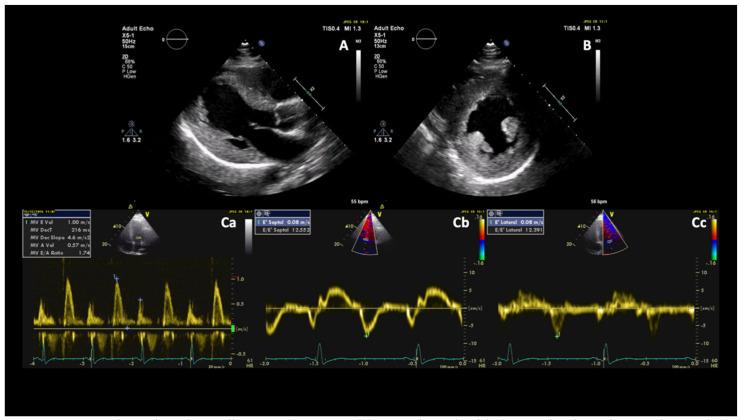

The mitochondrial myopathy, encephalopathy, lactic acidosis, and stroke-like episodes (MELAS) syndrome is an uncommon cause of cardiac hypertrophy, fibrosis, and dysfunction. It shares similar features to numerous other causes of left ventricular hypertrophy, and therefore, because of its rarity, may not be immediately considered as a diagnosis. Prompt recognition of clinical and cardiac imaging features may expedite diagnosis and management. We report the case of a 38-year-old man admitted with neurological symptoms and in whom the diagnostic workup led to the diagnosis of MELAS syndrome with cardiac involvement.

线粒体肌病、脑病、乳酸酸中毒和卒中样发作(MELAS)综合征是导致心脏肥大、纤维化和功能障碍的罕见病因。它与许多其他左心室肥大病因具有相似特征,因此,由于其罕见性,可能不会立即被考虑作为诊断。及时识别临床和心脏影像学特征可能会加快诊断和治疗。我们报告一例38岁男性患者,因神经症状入院,其诊断检查最终确诊为伴有心脏受累的MELAS综合征。